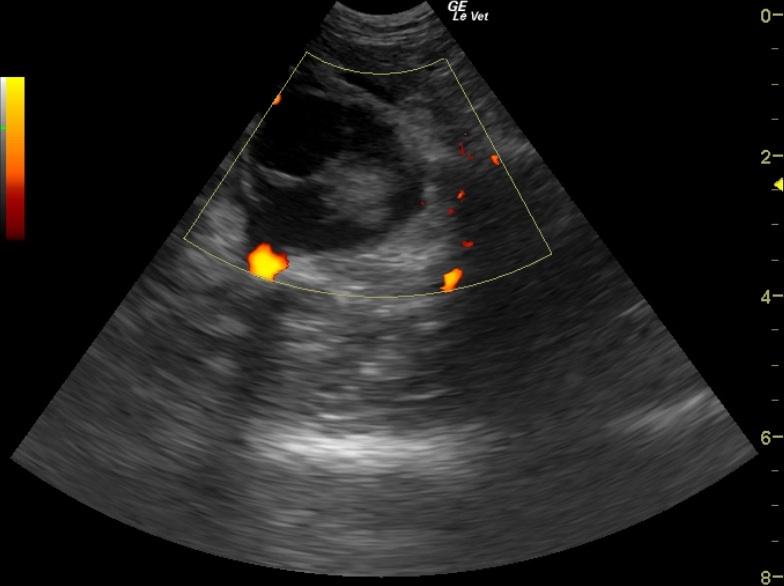

A 4-year-old MN DSH was presented for being not himself lately. Abnormalities on physical examination were increased respiratory effort and bilateral muffled heart sounds on auscultation. CBC, blood chemistry, and FeLV/FIV assay were all within normal limits. Thoracic radiographs showed pleural effusion with opacification of the heart. Approximately 80mls of turbid, hemorrhagic fluid was aspirated from both sides of the thorax, which on analysis was found to be an exudate. The patient was treated with Lasix and ampicillin.